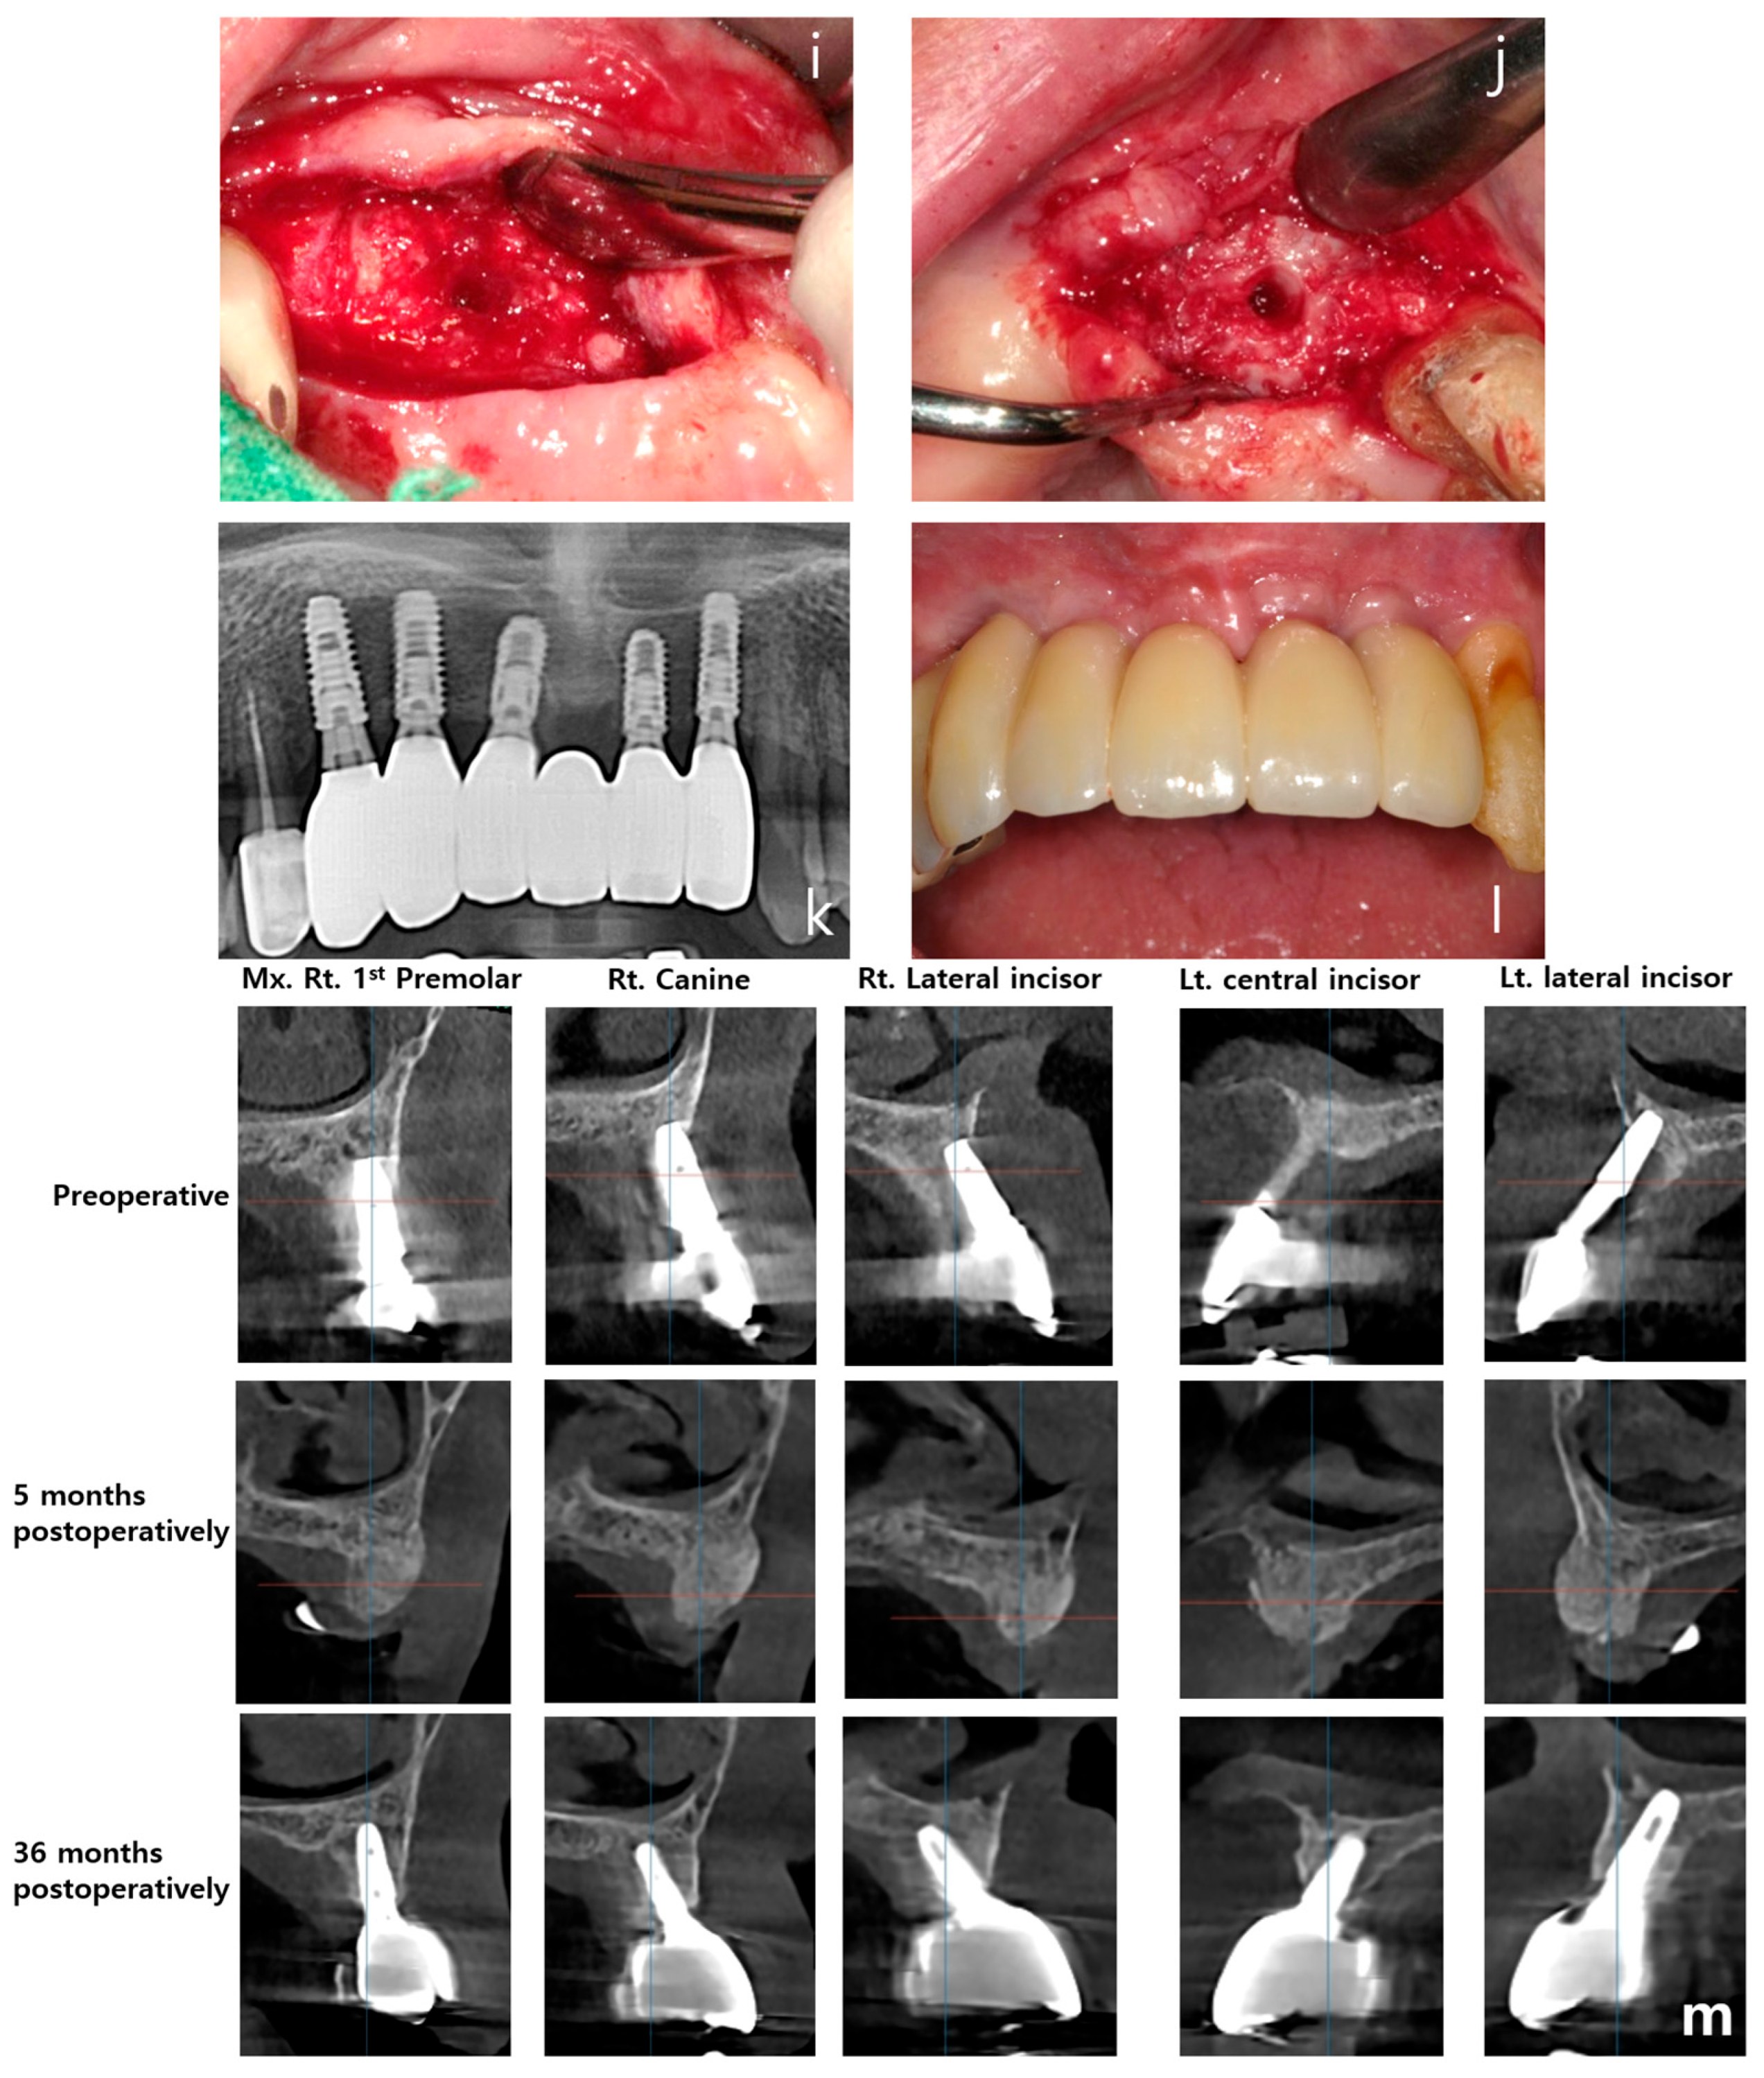

- Clinical efficacy: the combination of rhBMP-2 and a 3D-preformed titanium mesh (3D-PFTM) proved effective for reconstructing severely resorbed alveolar bone;

- Osteoinductive potential: rhBMP-2 demonstrated strong osteoinductive activity, even in patients with compromised bone regenerative capacity;

- Structural stability: the use of 3D-PFTM, particularly the OssBuilder system, provided reliable structural support for bone regeneration;

- Implant success: the combined approach resulted in stable bone regeneration and long-term implant success;

- Therapeutic value: the so called BOXAM (BMP-2, Oss-builder, xenograft, allograft, maintenance) technique appears to be a promising and reproducible strategy in dental and maxillofacial surgery.